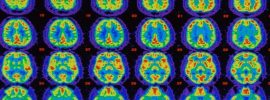

Ohromujúci objav neurovedcov o „bezdrôtovej“ komunikácii mozgu

Tím vedcov skúmajúcich mozog objavil celkom novú a doteraz neznámu formu „bezdrôtovej“ nervovej komunikácie, ktorá sa sama šíri mozgovým tkanivom. Je dokonca schopná preskakovať z neurónov v jednej časti mozgu do neurónov v druhej, a to aj vtedy, ak spojenie medzi nimi bolo prerušené.